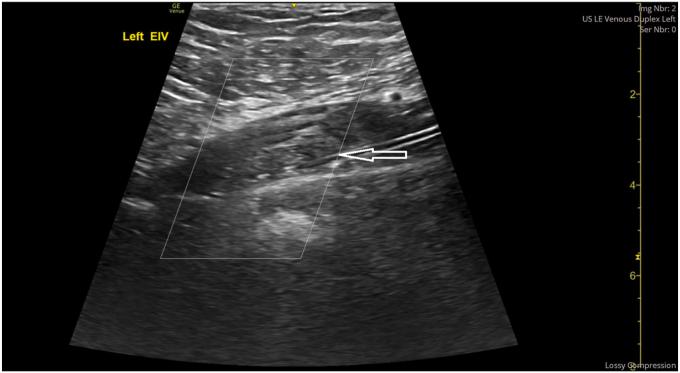

We present the case of a 20-year-old young man, with raised body mass index of >35 kg/m, who was initiated on tirzepatide treatment for weight loss, with 12-kg weight lost over 6 weeks. The patient did not have any risk factors for thrombophilia including family history, any recent travel, immobilization, recent infections, or recent surgeries. He presented with left leg swelling, and physical examination revealed signs of proximal DVT, and ultrasound Doppler and computed tomography venography confirmed extensive left-sided DVT with complete obstruction of the common femoral and iliac veins. He underwent mechanical thrombectomy and was maintained on anticoagulation therapy. His investigations for thrombophilia screening excluded any other cause for DVT, with the etiology attributed to possibly rapid weight loss.

我们报告一例20岁青年男性病例,其体重指数升高>35kg/m²,开始接受替尔泊肽治疗以减轻体重,6周内体重减轻12kg。该患者没有任何血栓形成倾向的危险因素,包括家族史、近期旅行、制动、近期感染或近期手术史。他出现左腿肿胀,体格检查发现近端DVT体征,超声多普勒和计算机断层静脉造影证实左侧广泛DVT,股总静脉和髂静脉完全阻塞。他接受了机械血栓切除术,并维持抗凝治疗。他的血栓形成倾向筛查排除了DVT的任何其他原因,病因可能归因于体重快速下降。